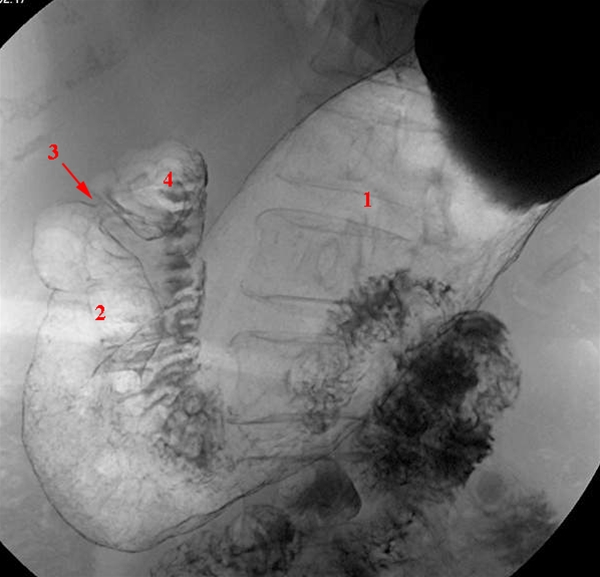

Mavesækken (ventriklen) vist på en røntgenundersøgelse med dobbelt kontrast-teknik med barium og luft - patienten i rygleje. Denne undersøgelse anvendes ikke så hyppigt idag - i stedet foretages CT-skanning.

1. Corpus ventriculi (mavesæk)

2. Antrum ventriculi (mavesæk nederste del)

3. Pylorus (maveporten)

4. Bulbus duodeni (tolvfingertarm)